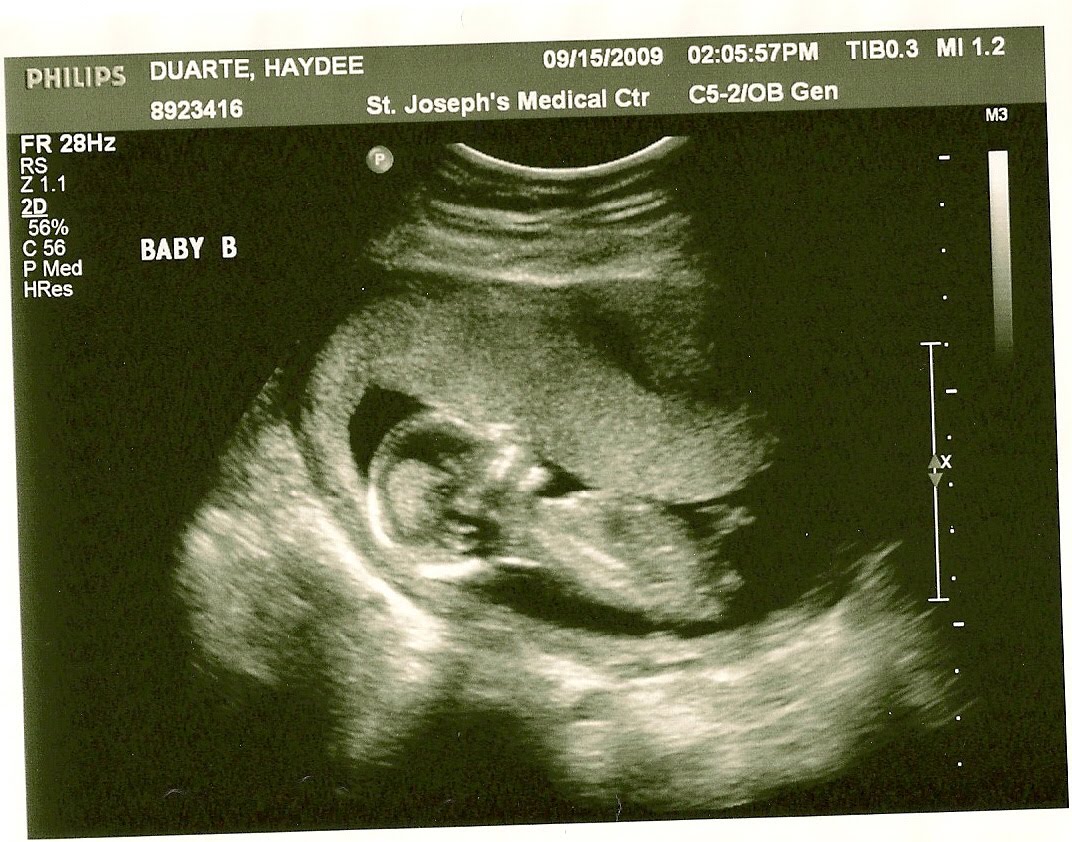

Here is the proof, in case you were wondering if we were pulling your leg or joking (as many do, when we share the news)! Have I mentioned that we don’t want to know the sex of the babies? We both think it will be a lot more fun to be surprised when they are born. So, in this case especially it was really nice to find out that the way the doctors keep track of both babies during my checkups is by calling them ‘Baby A’ and ‘Baby B’ — and they will be tracked like that throughout my entire pregnancy, so they will be able to monitor each baby’s growth and progress separately.

The pictures above were really fun. It was really the first time I could see them so clearly, instead of just looking at two little fuzzballs on the screen. I was shocked to see them positioned with their feet towards each other, but my doctor says they will do a whole lot more moving around before I deliver them. Although both of them wriggled around a lot during the ultrasound, Baby B was especially active–kicking and stretching its arms. So cute!

I hope you enjoyed your first glimpse at my little bundles of joy. I am bracing myself for a lot of kicking in the future. These days I just feel a few flutters here and there, so I can imagine how active they’ll both be as they grow bigger in my tummy.